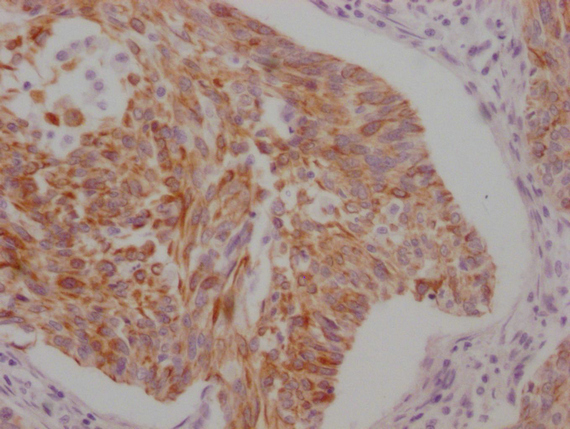

IHC image of CSB-MA898464 diluted at 1:100 and staining in paraffin-embedded human cervical cancer performed on a Leica BondTM system. After dewaxing and hydration, antigen retrieval was mediated by high pressure in a citrate buffer (pH 6.0). Section was blocked with 10% normal goat serum 30min at RT. Then primary antibody (1% BSA) was incubated at 4°C overnight. The primary is detected by a Goat anti-mouse IgG polymer labeled by HRP and visualized using 0.05% DAB.